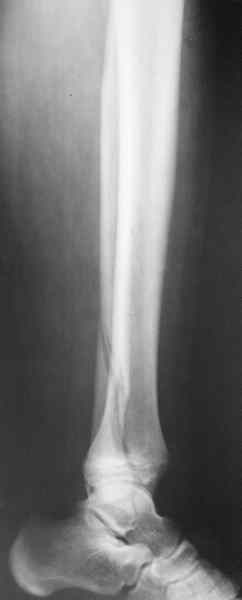

В приложении метафизарный перелом у ребёнка 14лет, с распространением линии перелома на зону роста.